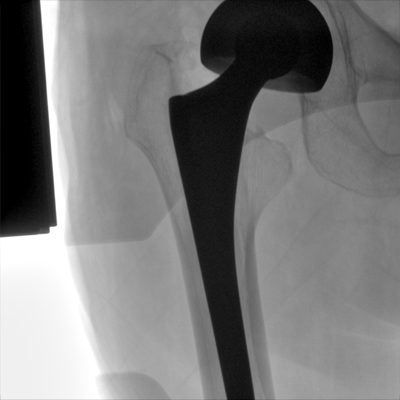

大尺寸液晶顯示器,圖像顯示清晰細(xì)膩;顯示器可大角度旋轉(zhuǎn),滿足臨床多角度觀察圖像的需要。